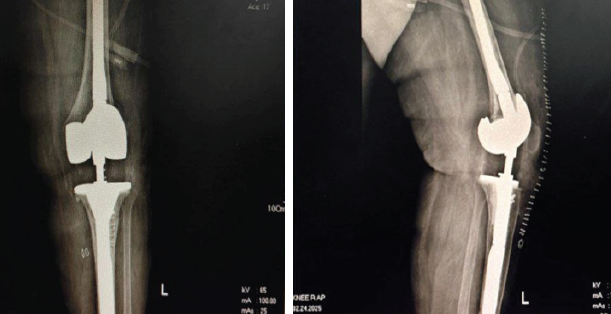

Following confirmation of infection eradication, definitive revision TKA was performed using a rotating hinge knee prosthesis (Fig. 4) due to ligamentous insufficiency and bone loss.

Figure 4: Immediate post-operative anteroposterior and lateral radiographs following revision total knee arthroplasty showing well-aligned and stable prosthetic components.

Rotating hinge knee prostheses have been shown to provide reliable stability and acceptable functional outcomes in complex revision total knee arthroplasty with severe ligamentous insufficiency. [17] Intraoperative cultures were sterile. Post-operative rehabilitation focused on gradual range-of-motion exercises and strengthening (Fig. 5). The Knee Society Score improved from 40 preoperatively to 86 postoperatively. Radiographs demonstrated stable implant fixation and satisfactory mechanical alignment. At the final follow-up of 20 months, the patient was pain-free, ambulating independently, and showed no evidence of recurrent infection.